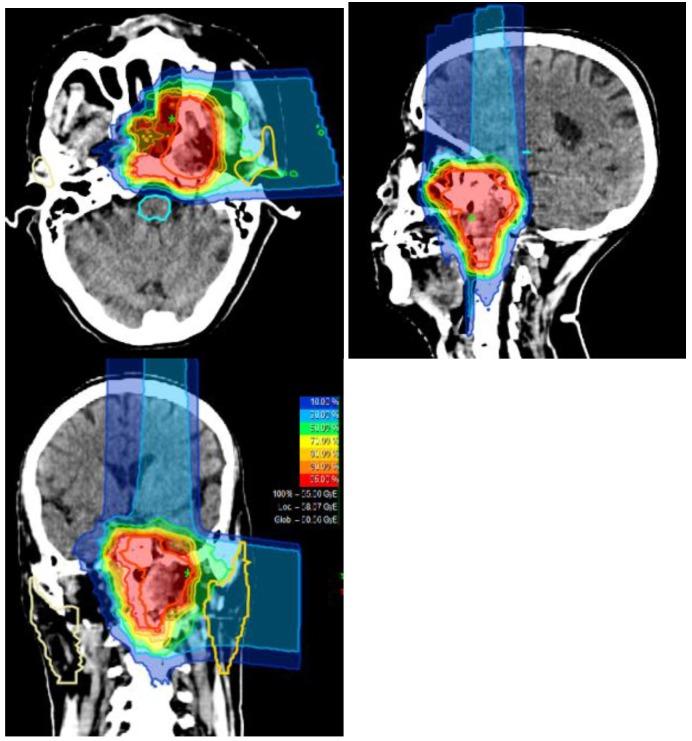

The recommended dose of re-irradiation using CIRT for locally recurrent NPC will be determined in the dose-escalating phase (Phase I) of the study. Efficacy in terms of local progression-free survival (LPFS) and overall survival (OS) will be studied in the second phase of the study. Increasing doses of CIRT using raster scanning technology from 55GyE (22×2.5 GyE) to 65 GyE (26× 2.5 GyE) will be delivered in the Phase I part of the study. The primary endpoint of the Phase I part of the study is acute and sub-acute toxicities; the primary endpoint in the Phase II part is local progression-free survival and overall survival. Using the historical 2-year OS rate of 50% in locally recurrent NPC patients treated with photon or proton, we hypothesize that CIRT can improve the 2-year OS rate to 70%.

在研究的剂量递增阶段(Ⅰ期)确定使用CIRT对局部复发性鼻咽癌进行再照射的推荐剂量。将在研究的第二阶段研究局部无进展生存期(LPFS)和总生存期(OS)方面的疗效。在研究的Ⅰ期部分,使用光栅扫描技术将CIRT剂量从55GyE(22×2.5GyE)增加到65GyE(26×2.5GyE)。研究Ⅰ期部分的主要终点是急性和亚急性毒性;Ⅱ期部分的主要终点是局部无进展生存期和总生存期。根据接受光子或质子治疗的局部复发性鼻咽癌患者的历史2年OS率为50%,我们假设CIRT可将2年OS率提高到70%。